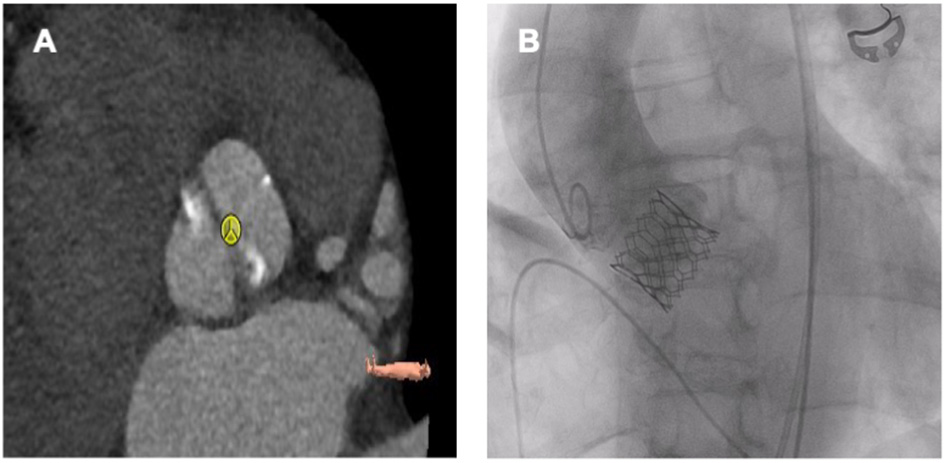

Figure 4

Sapien 3 Ultra 26 mm in a bicuspid aortic valve (Sievers Typ 1a R-L). (A) Preprocedural planning. (B) Fluoroscopy after TAVR.